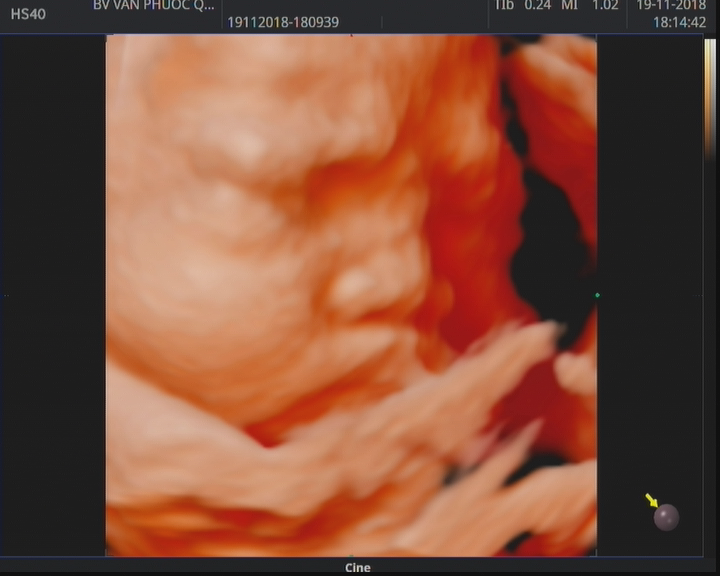

Hình ảnh siêu âm 5D tại bệnh viện Vạn Phước

HÃY ĐỂ CHÚNG TÔI GIÚP BẠN LƯU GIỮ NHỮNG HÌNH ẢNH ĐẸP NHẤT VỀ BÉ.